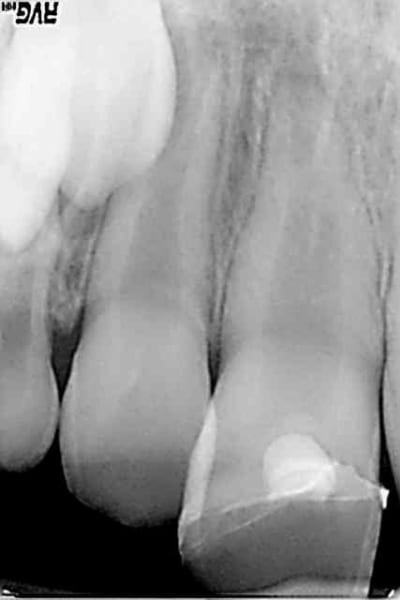

Cas concret, patient 8 ans fracture de la 11 avec effraction pulpaire. Traitement mta dans la chambre collage du morceau cassé et oh! miracle 8 mois après pont dentinaire et apexogenèse en branle. Cout 120 euros le sachet de mta. La sécu rembourse une pulpo à 16.87 euros juste de quoi mettre un eugenate et de découvrir l'apex béant avec en plus une bonne pèche 6 mois plus tard et dent nase. Les parents du patient vont témoigner sur lcp que les dépassements d'honoraires sont une honte ? Quel pays lamentable.